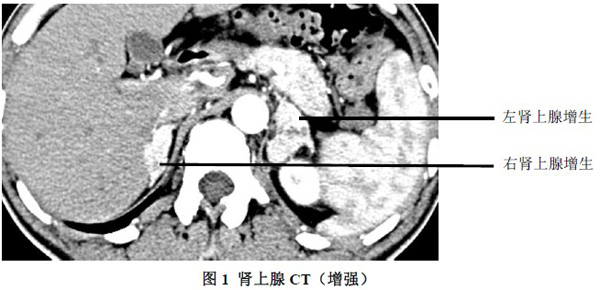

肾上腺分泌激素过多主要是垂体部位发生病变引起促肾上腺激素分泌增多,导致双侧肾上腺弥漫性增生而产生的疾病,总而言之,是机体内分泌系统出